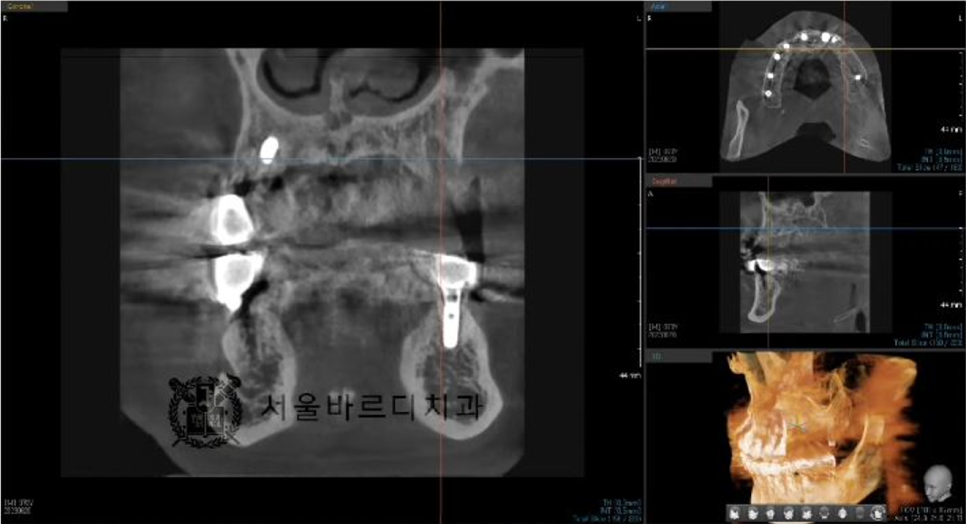

정확한 뼈 상태태를 확인하기 위해 수술전에

3D CT와 구강스캔데이터를 가지고 모의 수술을 해 본 후에

시뮬레이션 결과대로 임플란트 수술을 할 수 있게 하는

가이드 장치를 제작합니다

맞춤 장치를 제작하는 네비게이션 임플란트라고 하는데요.

더 안전하고 정확한 임플란트 수술을 위한 작업입니다.

20230711

빠진 임플란트와 그 옆에 하나 더 임플란트 시술을 하셨습니다.

임플란트 후에도 수술이 잘 되었는지

파노라마와 3D CT촬영으로 결과를 확인합니다.